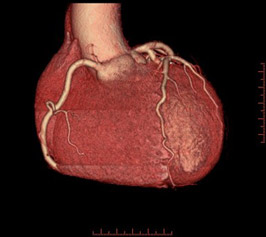

様々な画像表示処理方法を用い診断します。

ボリュームレンダリング